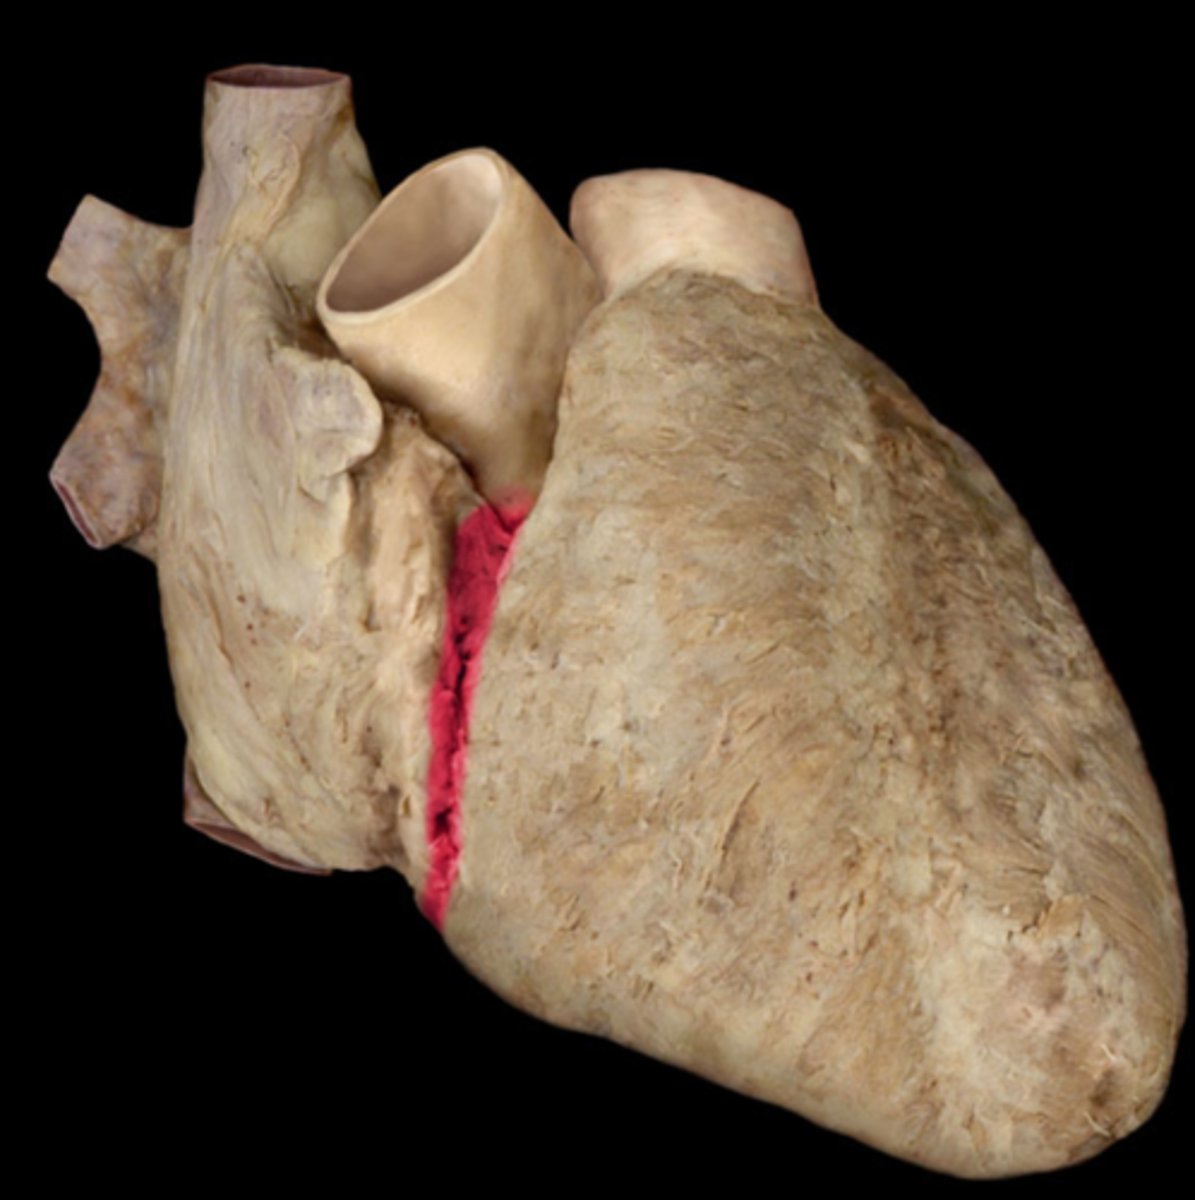

anterior interventricular sulcus

the junction between right and left ventricles

anterior side (depression)

anterior interventricular artery

in the anterior interventricular sulcus